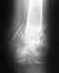

застарелый разрыв акромиального сочленения

Последствия травмы Отправлено илья 28 Январь 2012, 01:56

восемь лет назад получил травму в результате подения

после операции почувствовал,что рука "не на своём месте"лопатка стала выперать,но врач сказал,что всё в норме.я поехал в область и мне поставили диагноз(застарелый,невправленный вывих акромиального конца правой ключицы,смешанная контрактура правого плечевого сустава.операция 2.04.03г.)и предложили аутодермопластику по Скублену-Бому.от операции я отказался,потихоньку привык и разработал более-менее руку,но сейчас у меня страшные боли под лопаткой,болят и усыхают мыжцы груди и всёй руки вплоть до самых пальцев. ПОДСКАЖИТЕ ПОЖАЛУЙСТА,ЧТО МНЕ ДЕЛАТЬ мне 33года,но сердце пошаливает-я шахтёр.можно-ли обойтись без оперативного вмешательства?